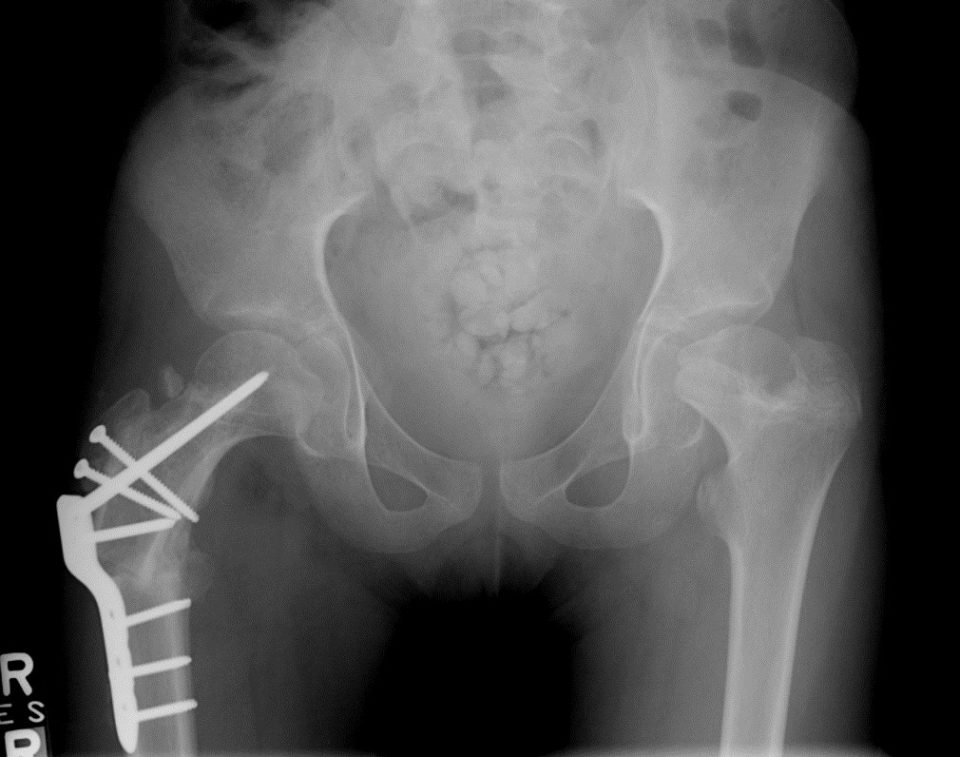

Bilateral Caput valgum, coxa vara, coxa breva corrected on the right side

Identical bilateral Caput valgum, coxa vara, coxa breva corrected on the right side with relative neck lengthening and Varus osteotomy.